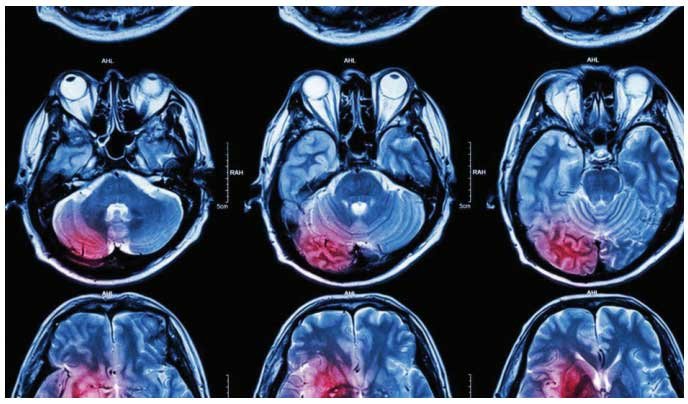

ബ്രെയിന് ട്യൂമര്, ചിലര് നിസാരമെന്നും ചിലര് ഭീകരമെന്നും കരുതുന്ന ഈ രോഗാവസ്ഥ അത്യധികം ശ്രദ്ധയോടെ കൈകാര്യം ചെയ്യേണ്ട ഒന്നാണ്. തലച്ചോറിനുള്ളിലെ അസാധാരണ കോശങ്ങളുടെ രൂപവത്കരണത്തെ ബ്രെയിന് ട്യൂമര് എന്ന വാക്കു കൊണ്ട് ഉദ്ദേശിക്കുന്നത്. മാരകമായ കാന്സര് മുഴകള്, അപകടകരമല്ലാത്ത മുഴകള് എന്നിങ്ങനെ രണ്ട് പ്രധാന തരം ബ്രെയിന് ട്യൂമറുകള് ആണ് ഉള്ളത്. തുടക്കത്തിലേ കണ്ടെത്തിയാല് മാത്രമേ മികച്ച ചികിത്സ ലഭ്യമാക്കാന് കഴിയൂ.

ബ്രെയിന് ട്യൂമര് – ഈ ഒരു വാക്ക് കേള്ക്കാത്തവരായ് ആരും തന്നെ ഉണ്ടാവില്ല. ഇന്ന് ഏറെക്കുറെ സ്വാഭാവികമായ ഒരു രോഗാവസ്ഥയായി പലരും ഇതിനെ കാണുന്നു. കാന്സറിന് കാരണമായ മുഴകളും അല്ലാത്തവയും തലച്ചോറില് കാണപ്പെടുന്നു. എതിരായും നേരത്തെ ഇത് കണ്ടെത്തുകയാണെങ്കില് അത്രയും മികച്ച ചികിത്സ ലഭ്യമാക്കാന് സാധിക്കും. മസ്തിഷ്ക മുഴകളില് അതിജീവിക്കാനുള്ള സാധ്യത താഴെ പറയുന്ന ഘടകങ്ങളെ ആശ്രയിച്ചിരിക്കുന്നു:

തലച്ചോറിന്റെ കംപ്രഷന് അല്ലെങ്കില് പ്രകോപനം മൂലമാണ് ട്യൂമറുകള് രോഗലക്ഷണങ്ങള് കാണിക്കുന്നത്. ഇവയുടെ പ്രധാന ലക്ഷണങ്ങള് എന്ന് പറയുന്നത് തലവേദന, ഫിറ്റ്സ്, കാഴ്ച സംബന്ധമായ പ്രശ്നങ്ങള്, ഛര്ദ്ദി, മസ്തിഷ്കത്തില് സംഭവിക്കുന്ന ന്യുനത്വം (സെന്സോറിയം കുറയുന്നത്), മാനസികമായ മാറ്റങ്ങള് എന്നിവയാണ്. ഇത്തരം അവസരങ്ങളില് രോഗിക്കു അസഹനീയമായ തലവേദന അനുഭവപ്പെടുന്നു. അത് രാവിലെ അതീതീവ്രമായി വരികയും ചിലപ്പോള് ഛര്ദ്ദിക്കുന്നതോടെ ശമിക്കുകയും ചെയ്യുന്നു. എന്നാല് ചില അവസരങ്ങളില് നടക്കാനോ അല്ലെങ്കില് സംസാരിക്കാനോ ഉള്ള ബുദ്ധിമുട്ട് ഉള്പ്പെടാം.